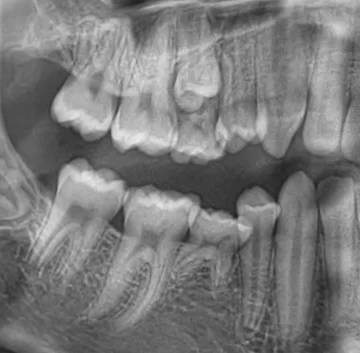

Biopsia reprezinta indepartarea chirurgicala a unei bucati de tesut din organism, cu scopul de a fi examinat microscopic in vederea stabilirii unui diagnostic corect.